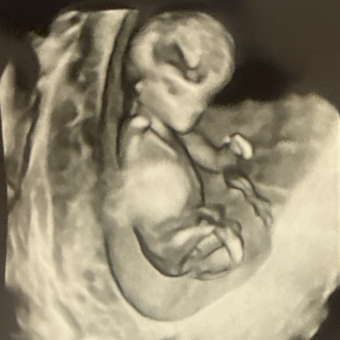

Hi friends and family! Please do not feel obligated to purchase anything. However, if you so wish... here is a shopping list we have put together. We look forward to spending time with you guys with baby Rowan. 😄